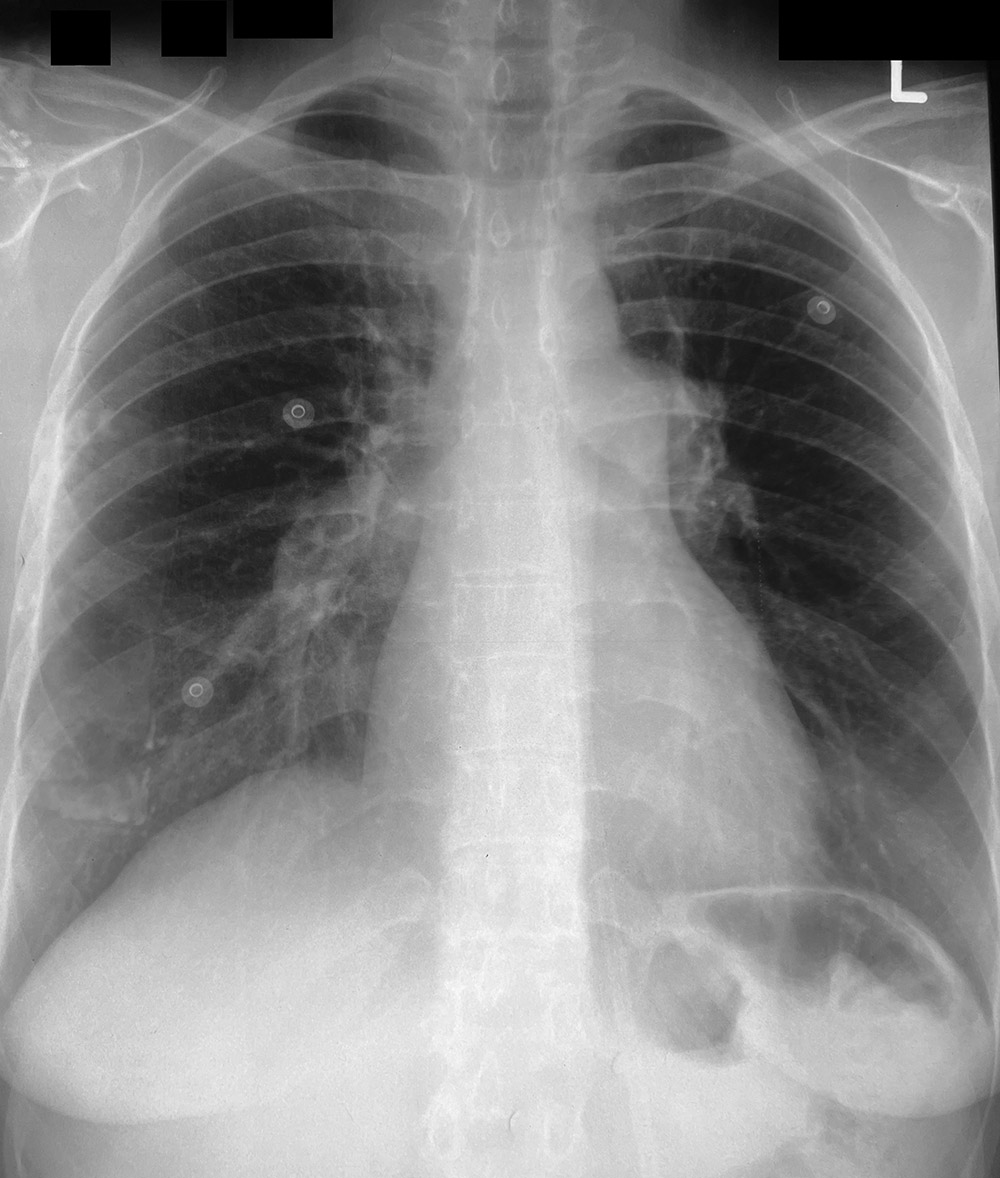

◂Chest CT for Internal Medicine Residents